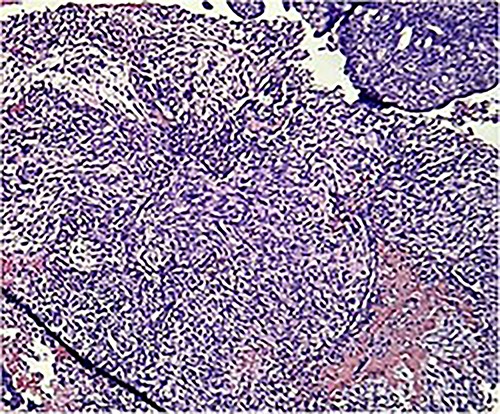

Macroscopically, an amorphous uterus weighing 397 g and measuring 12 × 9 × 7.5 cm with a brown serosa, and multinodular violaceous areas was examined. When incised, the endometrial cavity was occupied by a whitish polypoid mass of 8 × 5 cm which invaded the myometrium. In addition, multiple firm whitish nodules ~2 × 1.5 cm in diameter were identified. Bilateral ovaries and fallopian tubes appeared to be of normal morphology and size. Histologically, there was evidence of epithelial and sarcomatous components (Figs 1 and 2), and the epithelial component developed atypical glands (Fig. 3). The diagnosis of MMMT was given due to histologic findings.

Photomicrograph shows homologous sarcomatous components, composed of sarcomatous spindle shaped cells, with elongated nuclei and irregular nuclear membrane. (H&E stain ×10).